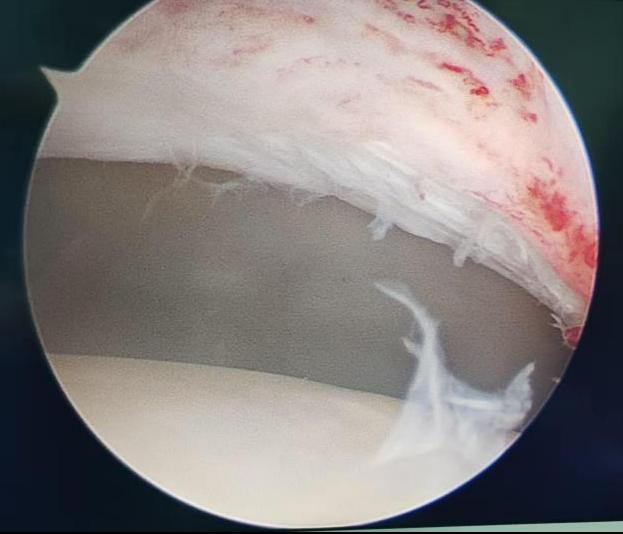

该病常伴随盂唇损伤,长期拖延会加重疼痛、加速关节退变。经充分评估与沟通,关节运动医学团队为王女士制定了微创、精准、快速康复的手术方案:关节镜下髋关节撞击股骨颈成形 + 盂唇修复术。经过术前检查,无手术禁忌,手术顺利开展,全程用时不到 1 小时。

4.镜下清晰视野,精准打磨增生骨质

5.完美修复损伤盂唇,重建髋关节正常结构